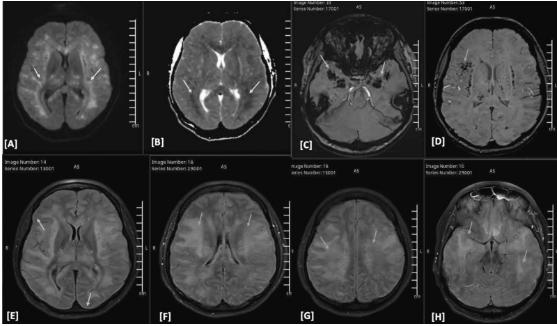

图2、头部核磁共振对比增强

(A-D)DWI/ADC序列显示颅内压增高、散在双侧白质、丘脑和脑干扩散受限以及双侧微出血的放射学证据

(E-H)FLAIR图像显示了增强后图像上注意到的双侧软脑膜强化和弥漫性脑水肿的证据。颅内血管造影不明显(未显示)。总体印象有利于急性播散性出血性脑炎

脑磁共振增强成像(MRI)显示弥漫性脑肿胀,颅内压升高,双侧白质分散,丘脑和脑干扩散受限,并伴有双侧微出血。对比后FLAIR图像显示双侧轻脑膜增强(图2)。这些发现证实了暴发性急性出血性脑白质脑炎/脑脊髓炎(AHLE/咳咳)的有效诊断。气管内新型冠状病毒RNA阳性,胸部X线和CT正常,增加了副感染新冠肺炎相关暴发性AHLE的可能性。传染病小组在第一天开始给患者静脉注射200mg负荷剂量的雷地昔韦,然后从第二天到第五天再注射100mmg,以治疗新冠肺炎感染。